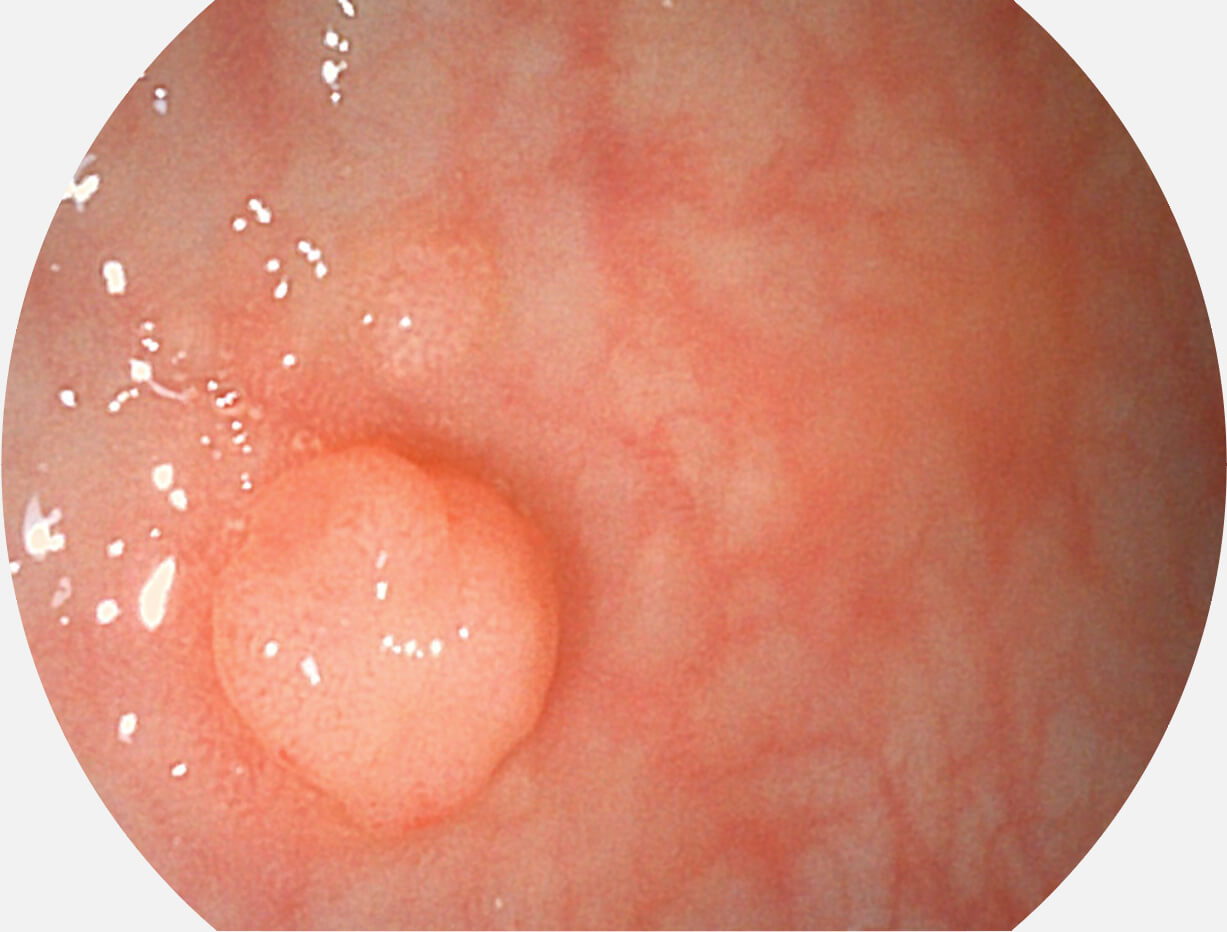

白光图像

VIST图像

Versatile Intelligent Staining Technology, VIST

强调浅层黏膜结构的同时,保证照明亮度和提升浅层微血管与中层血管颜色对比度,病变边界更清晰。